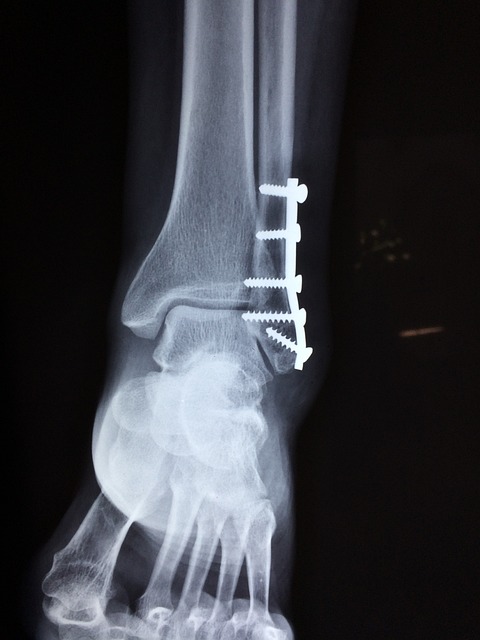

병원 치료: 사고 후 병원에 방문하여 X-ray 등 검사를 받아 부상 부위를 확인하고, 치료를 시작합니다. 골절, 타박상, 뇌진탕 등 상황에 맞는 치료를 받습니다.